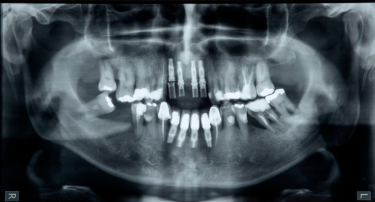

Radiografia panoramica e periapicais

A radiografia panorâmica oferece uma

visão geral de todos os dentes e

estruturas ao redor, sendo útil para

diagnósticos e planejamento de

tratamentos como implantes e ortodontia.

Já a radiografia periapical focada em um

dente específico, ideal para detectar

problemas nas raízes ou cáries profundas.